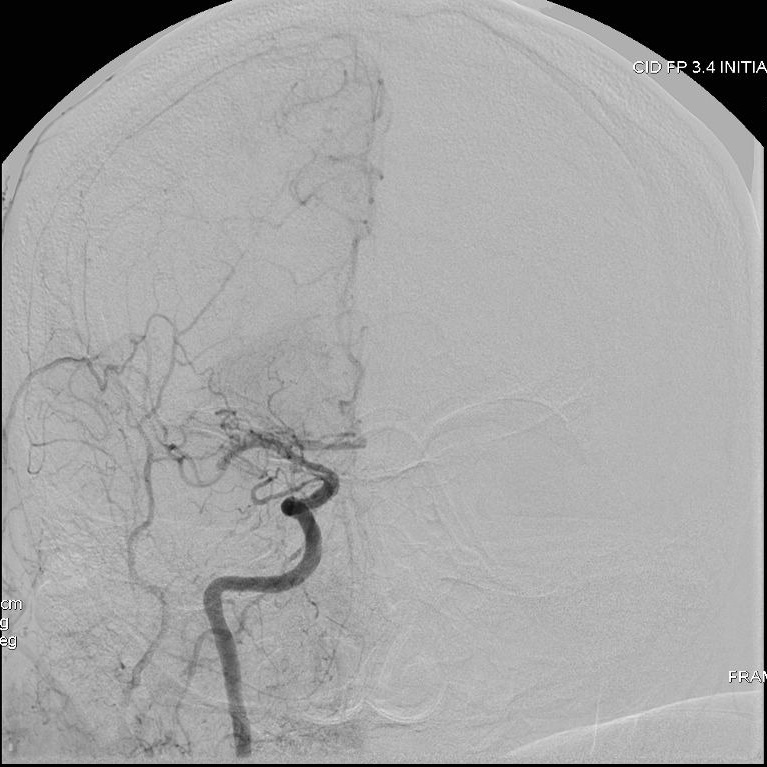

Patient présentant un AVCAccident Vasculaire cérébral : un déficit neurologique soudain d'origine vasculaire causé par un infarctus ou une hémorragie au niveau du cerveau https://fr.wikipedia.org/wiki/Accident_vasculaire_cérébral More ischémique aigue droit en rapport avec une occlusion proximale de l’artère cérébrale moyenne. Thrombolyseconsiste à lyser (désagréger) par médicament les thrombus (caillots sanguins) obstruant les vaisseaux sanguins https://fr.wikipedia.org/wiki/Thrombolyse More intraveineuse puis thrombectomieretrait mécanique d'un thrombus (synonyme de caillot sanguin) dans un vaisseau sanguin, veine ou artère https://fr.wikipedia.org/wiki/Thrombectomie More par voie endovasculaire retrouvant cette occlusion proximale. Reperfusion rapide permettant de limiter l’extension de l’AVCAccident Vasculaire cérébral : un déficit neurologique soudain d'origine vasculaire causé par un infarctus ou une hémorragie au niveau du cerveau https://fr.wikipedia.org/wiki/Accident_vasculaire_cérébral More ischémique et les séquelles neurologiques.